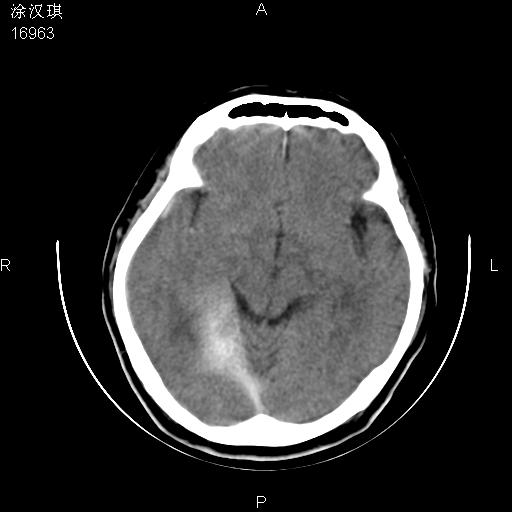

以下是引用chinazhouhua在2008-5-1 12:06:00的发言:[br]影像上来看,这是个典型的硬膜下血肿,包括右侧额颞部、大脑镰下、小脑幕下,而且在右侧额颞顶枕部、大脑镰下没看到高密度出血向脑沟内延伸,但是小脑幕下硬膜下有时候和蛛血不是很好鉴别,而且硬膜下很多时候伴有蛛血,往往在复查的时候出来,所以这种病人还是应该考虑硬膜下血肿伴有蛛血。

以下是引用zsl6918在2008-5-1 15:34:00的发言:[br]本病例主要表现为急性硬膜下血肿。

以下是引用形影不离在2008-5-1 11:32:00的发言:[br]支持 硬膜下血肿伴蛛网膜下腔出血,建议短期复查。

以下是引用wansheng在2008-5-1 11:20:00的发言:[br]支持硬膜下血肿伴蛛网膜下腔出血,建议短期复查